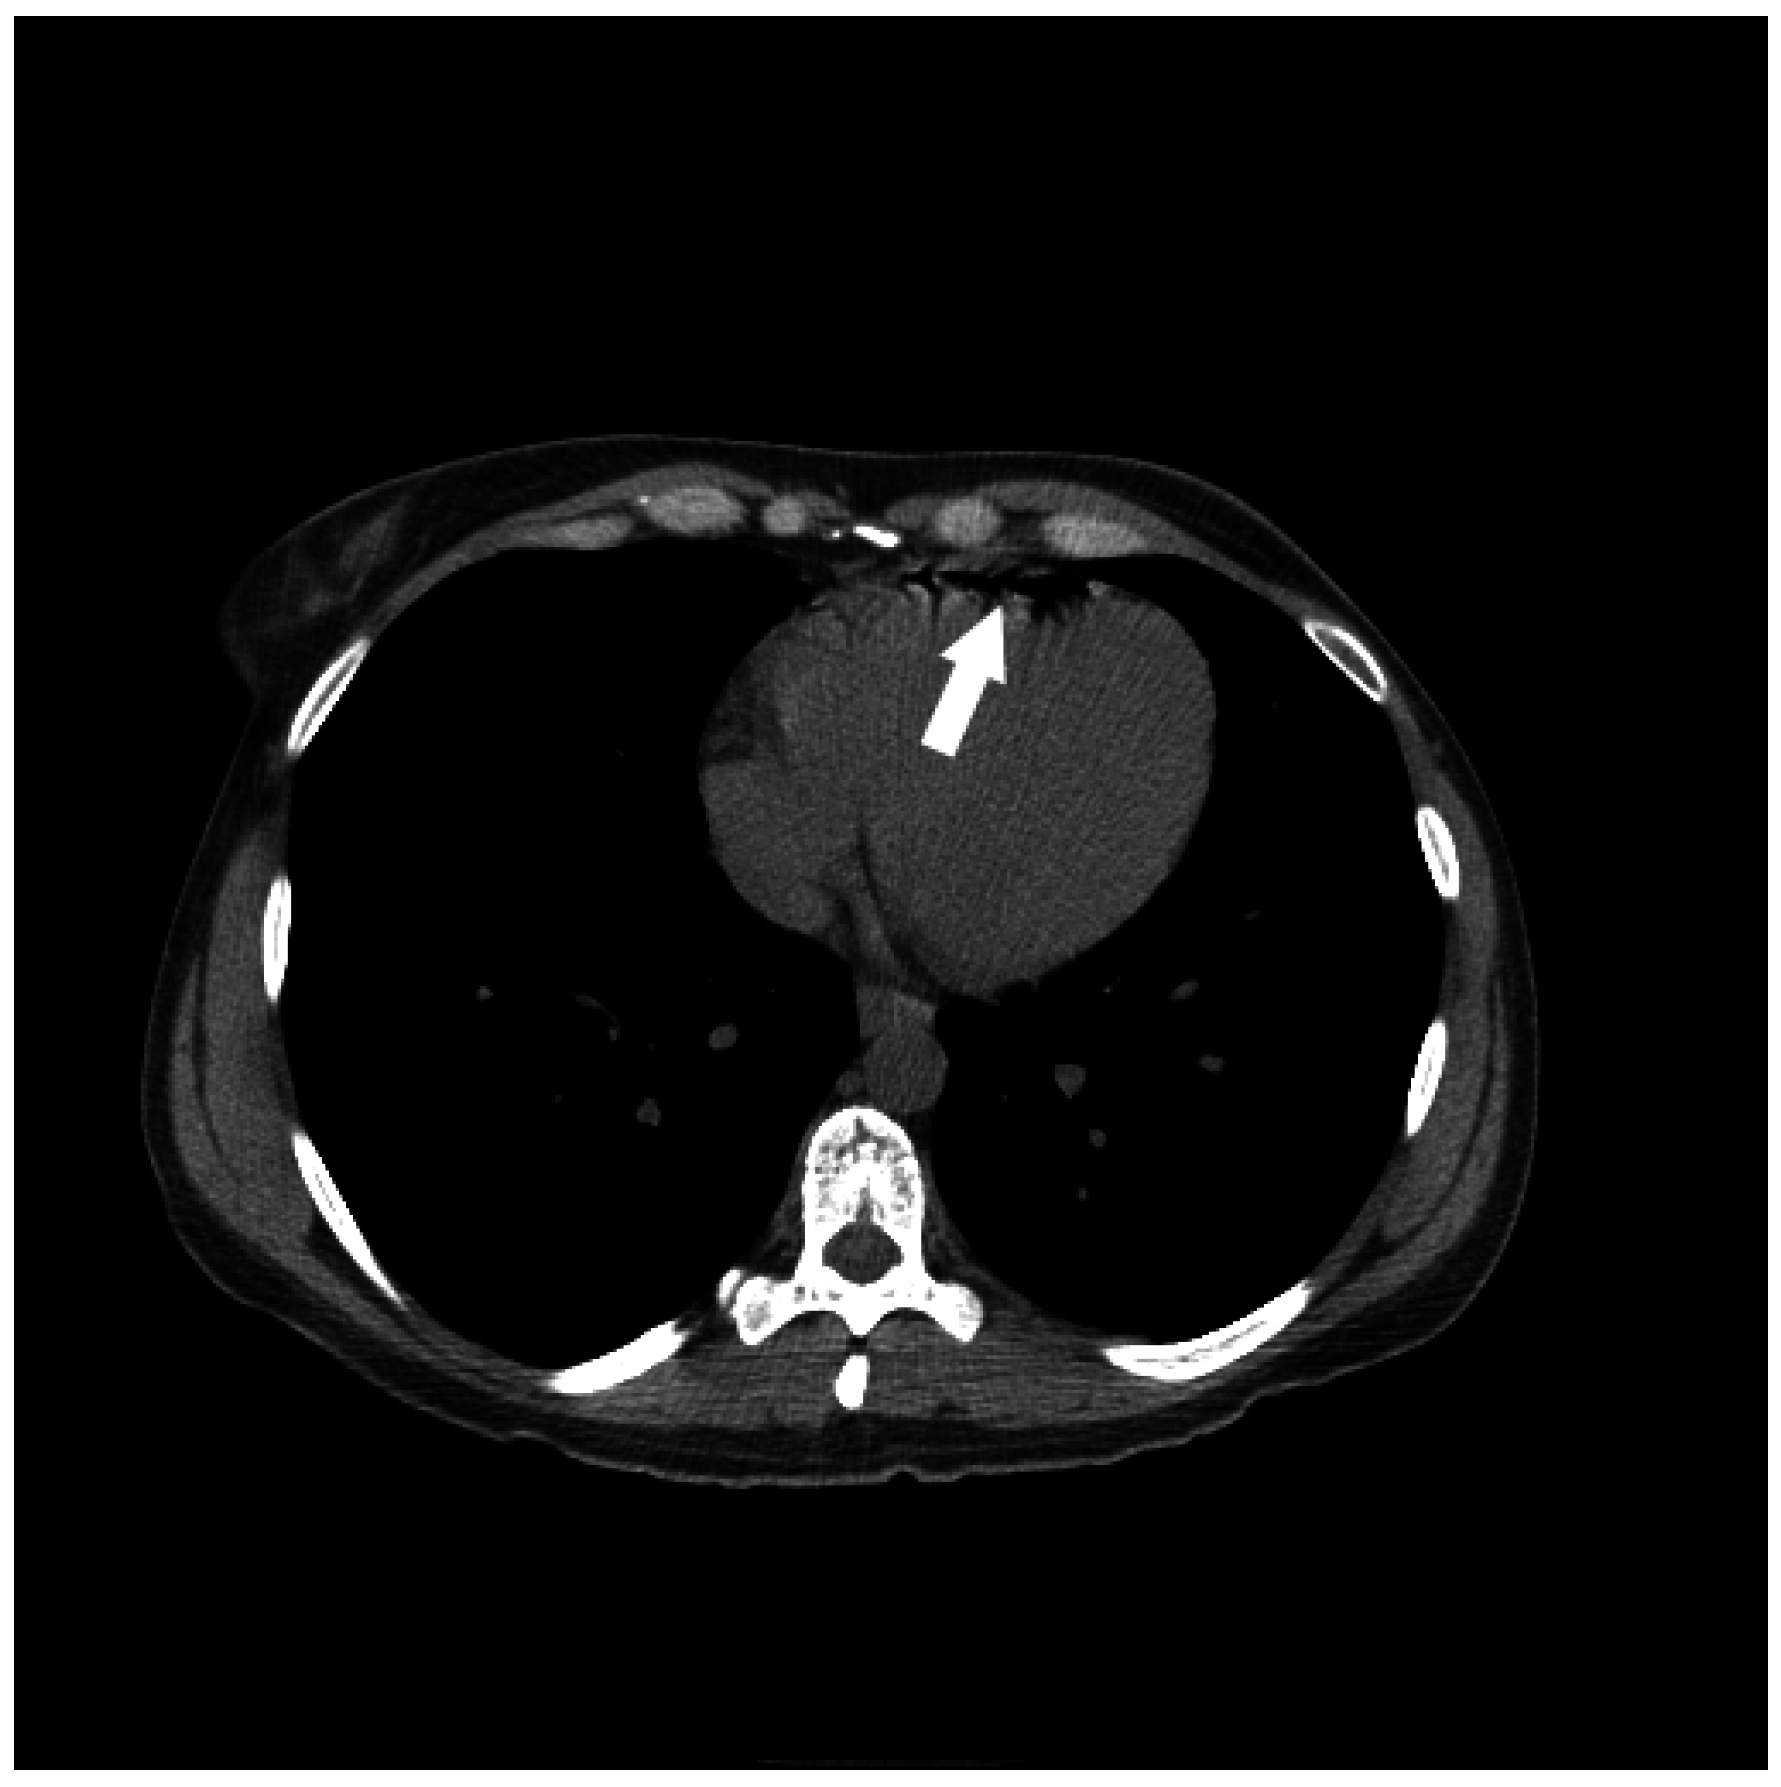

Figure 10.

The successful use of a hyperbaric oxygen therapy (HBOT) is outlined in this case, in which a 69-year-old female with a history of suspected lung cancer underwent a CT-guided lung biopsy at an outside facility (a). During the procedure, the patient suffered a cardiorespiratory arrest. An immediate CT (b) revealed a right pneumothorax (arrow), together with air in the right pulmonary vein (arrowhead). Additional images from the CT scan (c,d), revealed air in the right coronary artery (black arrow), the ascending thoracic aorta (white arrow) and the epidural veins (arrowhead). The patient was initially unresponsive and required cardiopulmonary resuscitation. A non-contrast CT brain (e) was performed, revealing air scattered in the vessels overlying the right cerebral hemisphere (arrowheads). Subsequent MRI of the brain confirmed multiple areas of acute infarction in the right cerebral and cerebellar hemispheres. Axial T2 (f) and DWI (g) images of the brain demonstrated acute areas of infarction in the right cerebellum. The patient required ICU management and HBOT.